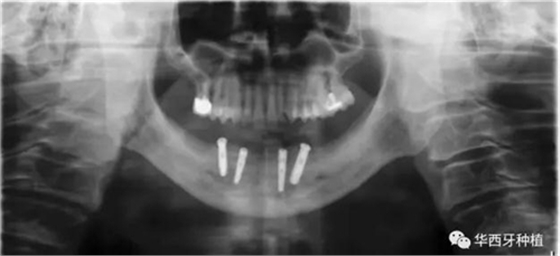

對于骨質(zhì)較差的患者,種植覆蓋義齒修復(fù)與all-on-four或all-on-six修復(fù),則更為適合。

吳教授特別針對手術(shù)難度更大的all-on-four修復(fù)做了詳細(xì)的關(guān)于概念、設(shè)計(jì)、操作、修復(fù)的描述,首先是針對難度最大的手術(shù)環(huán)節(jié),就解剖、微創(chuàng)操作分別加以闡述。將他自己在臨床工作中的寶貴經(jīng)驗(yàn)分享給了大家。

對于傳統(tǒng)的all-on-four術(shù)式,吳教授加入了微創(chuàng)的指導(dǎo)思想,設(shè)計(jì)時(shí)同樣加入數(shù)字化三維重建與修復(fù)一體化設(shè)計(jì),增加了手術(shù)的可控性,同時(shí)極大減輕了患者的創(chuàng)傷程度,縮短了修復(fù)周期。